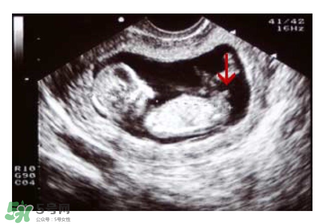

b超怎么看胎兒性別之看形狀

媽媽們可以在懷孕兩個(gè)月的時(shí)候去做B超,如果寶寶的形狀是長型的,像茄子或長條狀的,那么很有可能是男寶寶,若是橢圓或是圓型,那么可能是女寶寶。

如果媽媽是孕晚期,也可以看B超圖,對(duì)著你的,一般是女寶寶,背著的,一般是男寶寶。